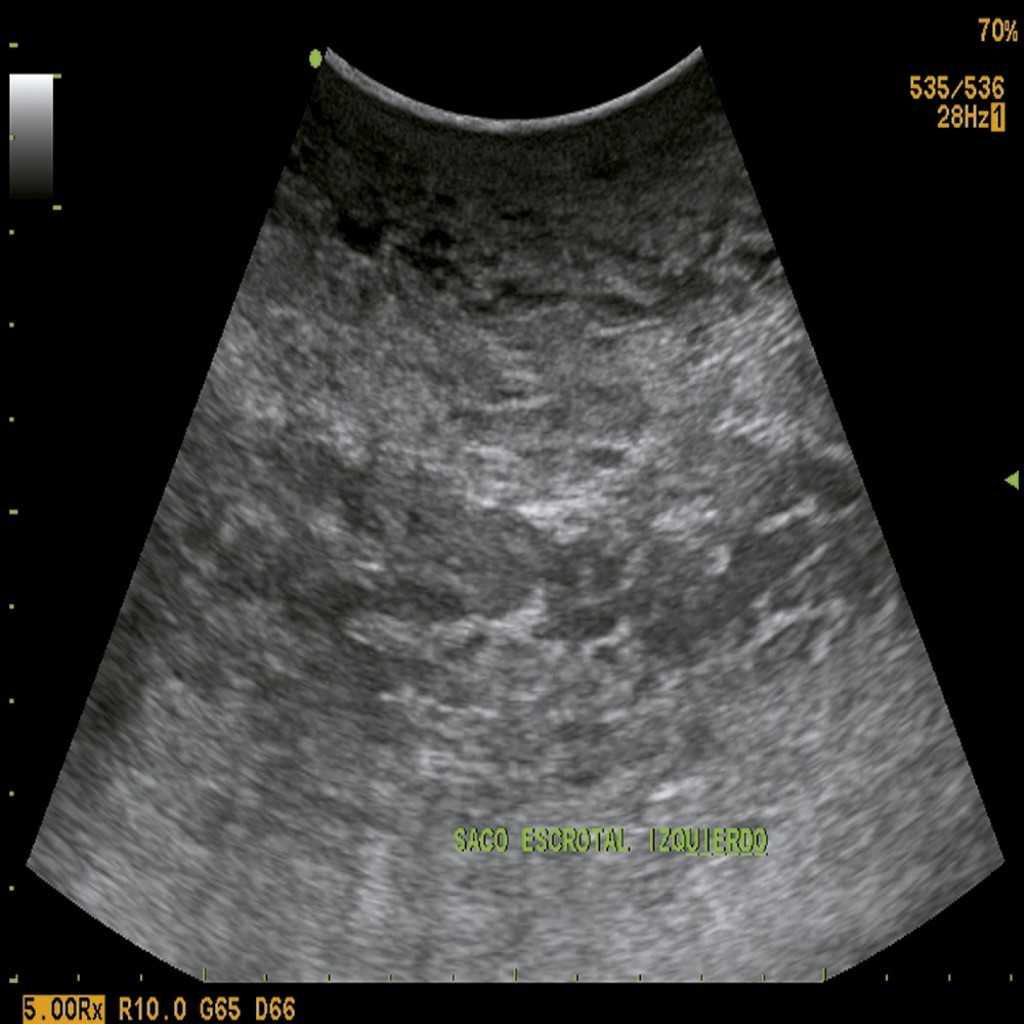

A 32-year-old male Mexican patient of mestizo ethnicity, a cab driver with a personal history of a sedentary lifestyle, and morbid obesity (body mass index [BMI] = 57), came for consultation for presenting a left inguinoscrotal hernia of 10 years of evolution. Physical examination confirmed that the patient had an inguinoscrotal hernia exceeding the upper border of the left patella and trophic changes of the scrotal skin (Figure 1). Inguinal ultrasound showed a hernial sac with intestinal and omental contents. He was started on NPP during his hospital stay by inserting a Veress needle at Palmer's point. 200 cm3 of room air was insufflated with a 100 cm syringe.3 Subsequently, a double-lumen catheter (subclavian) was placed with the Seldinger technique. An 800 cm3 of room air was insufflated, and a standing chest X-ray corroborated pneumoperitoneum. 1,000 cm3 were administered every 24 hours for 21 days up to a total volume of 21,000 cm3.

Figure 1